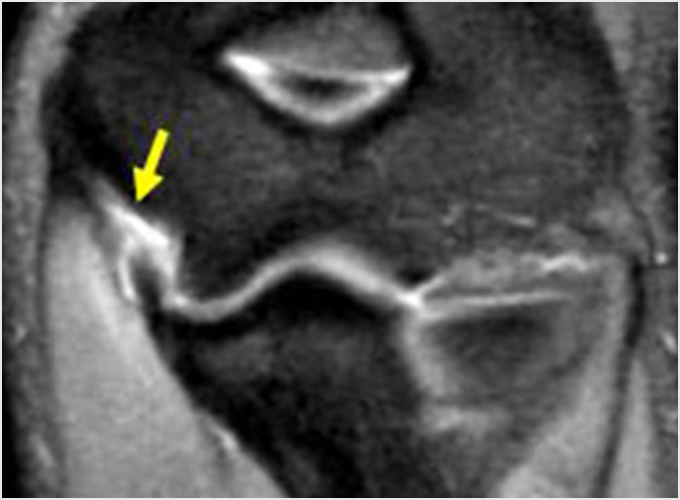

離断性骨軟骨炎(上腕骨小頭障害)

野球肘で最も重症になる障がいの1つです。ひどくなると関節軟骨の一部がはがれて関節ネズミとなったり、肘が変形して動きが悪くなったりします。初期に発見されれば投球禁止で治り、手術はしなくてもすむ場合が多いのですが、末期になると手術が必要となり、手術をしても肘の動きの制限や変形が残ってしまうこともあります。10歳前後で発症することが多いのですが、初期には自覚症状がないことが多く、13-17歳ごろにグラグラになった軟骨がはがれて痛みが出て初めて医療機関を受診されることもよくあります。 手術となった場合には骨の成長の度合い、病変の進行具合、病変の大きさなどにより手術方法が変わります。軟骨が安定している場合には軟骨を固定する手術を行う場合が多いです。軟骨がはがれている場合、病変が小さければ関節鏡を用いてはがれた、あるははがれかけている軟骨を摘出します(図4a)。病変の直径が1㎝以上であれば切開手術で膝の軟骨を病変部に移植します(図4b)。 最近全国各地で少年野球検診が行われるようになりましたが、一番の目的は離断性骨軟骨炎を早期に発見し、重症になる前に治療を行うことなのです。平成28年から多くの医師、理学療法士の協力により名古屋でも行われるようになりました。私も検診に参加し、エコーでのチェックを担当しました。およそ100人に1-2人の割合で発見されました。